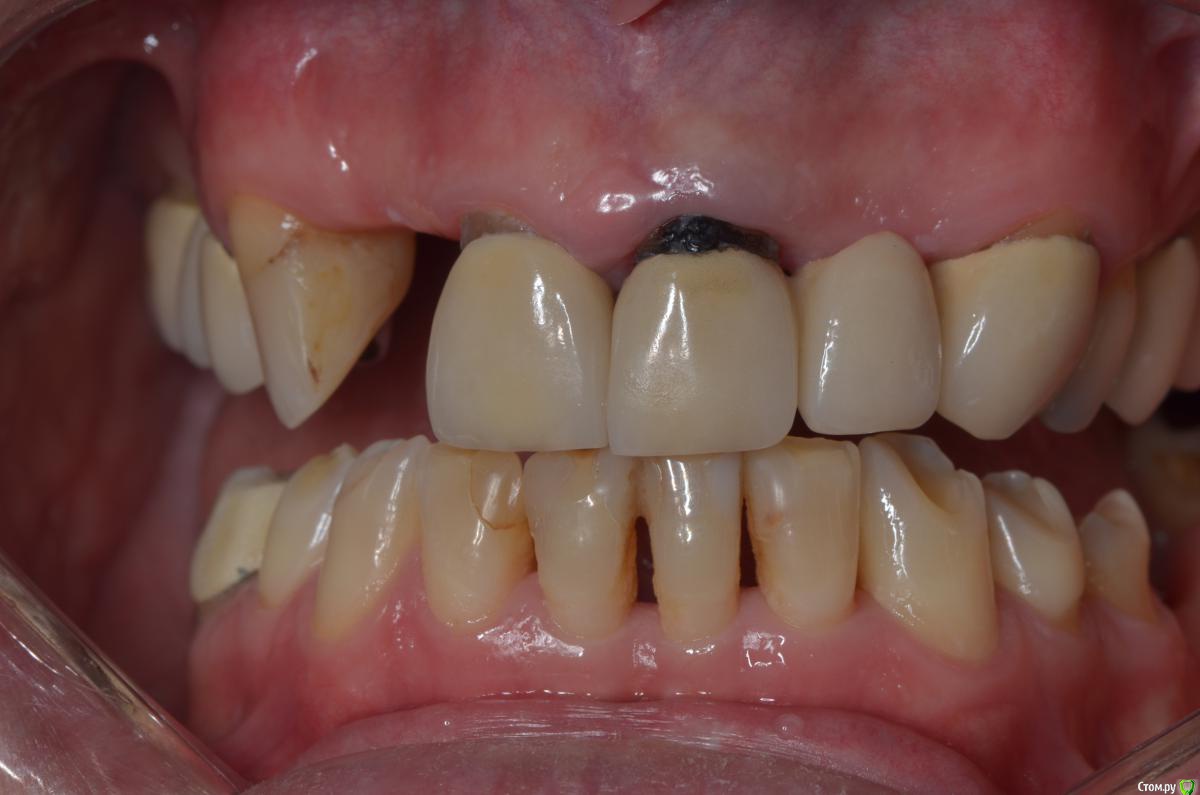

gangsta85 Опубликовано 27 сентября, 2016 Поделиться Опубликовано 27 сентября, 2016 Здравствуйте, уважаемые коллеги.Помогите пожалуйста разобраться.Центральные резцы в\ч были удалены и установлено 2 имплантата с пластикой десны, 12,22 отсутствуют в области 12 трансплантация слизистого лоскута.В тот же день изготовлены времянки по ключу с ваксапа. профиль трансгингивальной части сделан максимально под размер постоянной реставрации. 12,22 овоиды плотно прилегающие к десне.Вопросы:- Можно ли изготовить времянки сразу по форме максимально похожей на будущие реставраций и свести к минимуму коррекции профиля десны?- можно ли сделать надрез в области 22 и максимально погрузить в десну овоид 22, насколько плотно можно прижать овоид 11 в области слизистого трансплантата?- можно ли в такой ситуации добиться формирования десневых сосочков в области 12,22?-через какое время можно снять времянки для коррекции?- постоянная реставрация через 4 месяца? Что если снять слепок в день операции в лаборатории отфрезеровать времянки и установить через 1-2 дня , удастся ли в программе отмоделировать правильный профиль десны и овоиды? Как бы вы предпочли сделать времянки на CAD\CAM или в ручную? Ссылка на комментарий